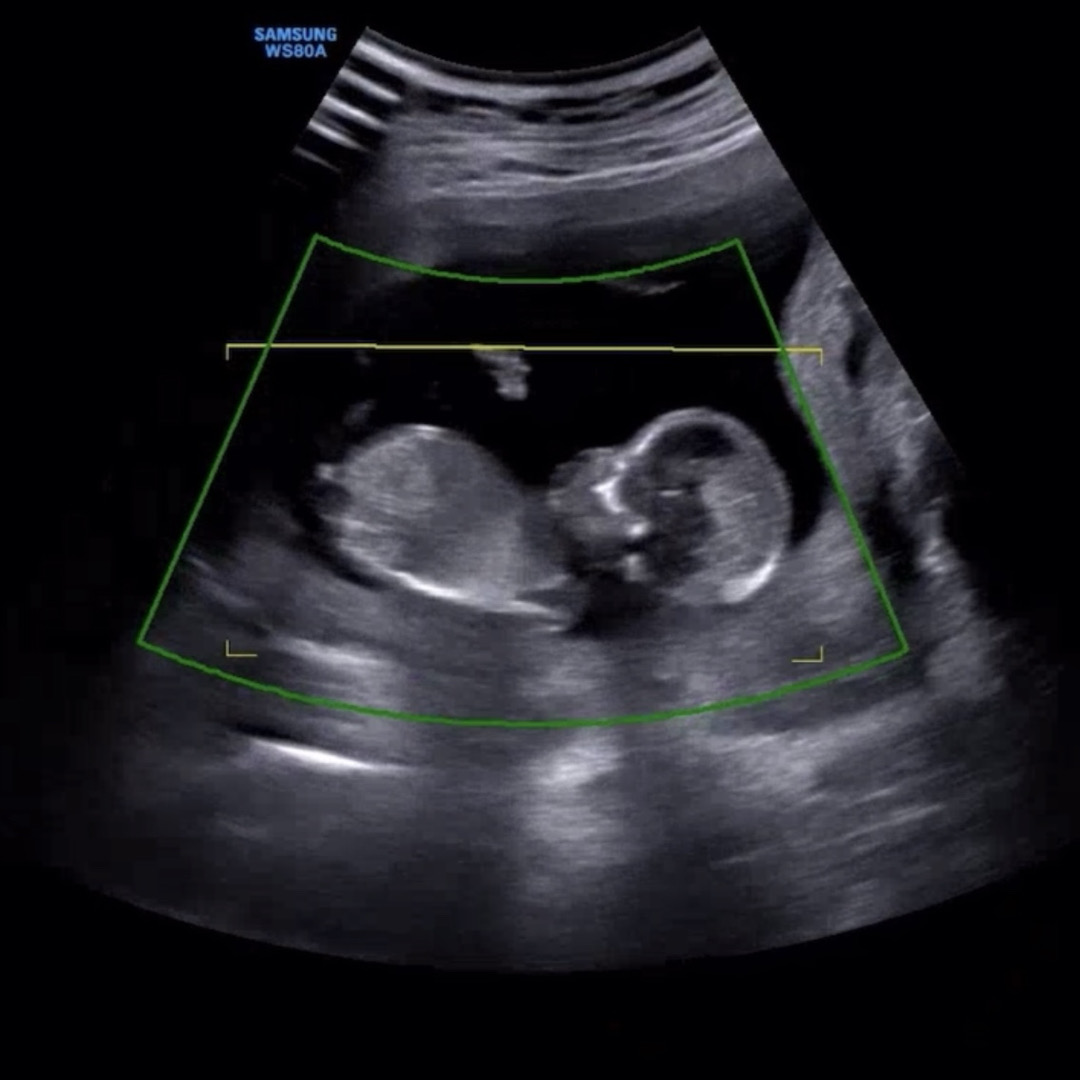

우리 둘째 성별 투표 부탁드려요♥️

다음 병원 진료가 한달뒤라 궁금해서 ㅎㅎ! 부탁드려요 ! 🫶🏻